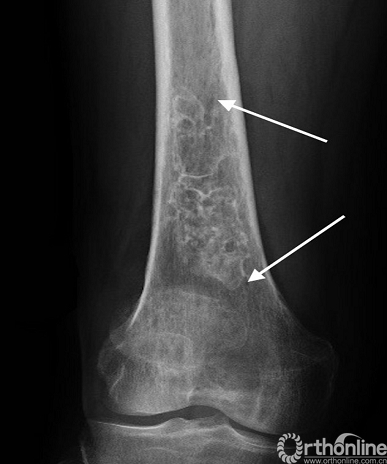

鉴别诊断:1.骨髓梗死:骨髓梗死通常会呈现较长的纵向病变,从而产生“烟囱中的烟雾”样外观(图7)。在MRI上,两者的区别更明显,软骨在T2上显示高信号。内生软骨瘤呈小叶样生长,而骨髓梗死中呈纵向“烟囱中的烟雾”样。2.软骨肉瘤:特征性表现包括疼痛持续缓慢恶化,体积大,有骨膜反应或皮质被突破(图8)。在手足中极为罕见,可见于扁平骨(如骨盆,肩胛骨和肋骨)。

图7 .骨髓梗死(箭头),股骨远端表现为纵向范围小束状的病变,钙化病灶呈“烟囱中的烟雾”样(smoke in chimney)。